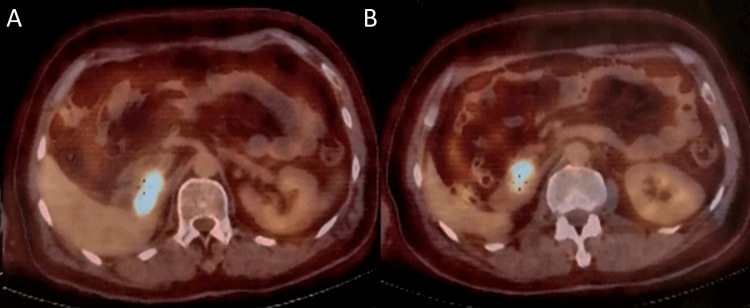

Hence, he was put on nivolumab for six months and at the end of the treatment he showed complete radiologic response according to Response Evaluation Criteria in Solid Tumors (RECIST) in the lungs and the brain, as well as complete resolution of metastatic lesions in the abdominal wall and liver, except for the persistence of a mass in duodenohepatic region (Figure 4).

Unfortunately, nivolumab was discontinued because of financial limitations. He was started on bevacizumab 400 mg every two weeks and was on maintenance bevacizumab for 22 months. On July 2022 the patient became icteric again with high levels of direct bilirubin. A CT scan revealed an 82×50×35 mm mass in the duodenohepatic region compressing the common bile duct (CBD), with no other sign of metastatic lesions in the chest, brain or abdominopelvic CT scans (Figures 5, 6). He is now being managed by a multidisciplinary team to determine the next therapeutic options.